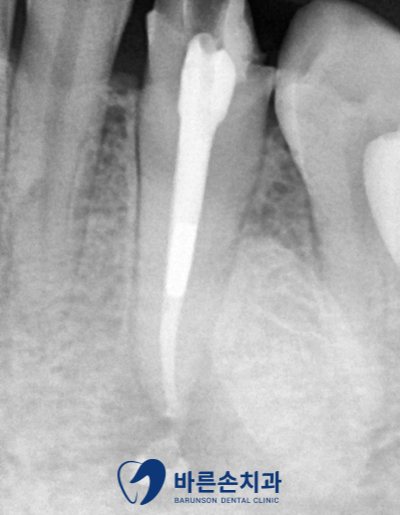

안녕하세요. 의정부 <바른손 치과>입니다. 오늘은 재신경치료에 대해서 설명드리겠습니다! 신경치료 한 치아에 염증이 발생됐다며 오신 환자분입니다. 파노라마 사진 상에 화살표 부분 보시면! 치아 뿌리 끝에 둥글게 까만색 원이 보이시나요?? 이미 신경 치료가 된 치아인데 염증이 생겼습니다… 통증도 있다고 하셨어요.. 자세히 보니 끝까지 신경치료가 완벽히 된게 아니였습니다. 그렇기 때문에 다시 한번 치아를 살려보자! 해서 재 신경치료를 진행했습니다. 먼저 치아 안에 충전되어있던 재료를 다 제거하고 다시 깨끗한 상태로 만듭니다. 염증도 엄청 많으셨고 발치 가능성도 있다고 설명드렸습니다. 신경관 안에 흰색 금속 무언가가 보였는데요. 제거는 되지 않았지만, 막힌 신경관을 확보하여 기구가 신경관 끝까지 들어가기 때문에 신경치료에는 문제가 되지 않았습니다! 수차례 소독과 배농 후 통증이 사라지셔서 신경관을 GP 콘 이라는 재료로 뿌리끝까지 채웠습니다. 남아있는 치아 머리 부분이 얼마 없기에 기둥(포스트)이 필요하셨고 레진으로 치아 벽도 만들었습니다. 크라운 제작을 위해 본을 뜨고 임시치아도 만들어드린 후 보철물이 제작될 때까지 일주일 정도 시간이 필요했어요. 이렇게 크라운도 씌우고 재신경치료를 마무리했습니다!! 앞으로 아무 통증 없이 잘 쓰셨으면 좋겠네요^^ 신경치료 후 염증이 생긴다고 해서 다 발치로 이어지지는 않습니다. 3D CT 촬영을 통해, 진단 후 재신경치료로 다시 살리는 경우가 많거든요!! 특히 오늘 알아본 케이스와 같이, 앞니의 경우에는 간단히 끝나는 경우도 많습니다!^^ 이렇게 재신경치료에 대해 보셨는데요! 다른 게시글에도 재신경치료의 내용이 있으니 참고해주세요~ 감사합니다^^ #의정부바른손치과 #신곡동바른손치과 #의정부치과추천 #의정부신경치료 #의정부보철치료 #의정부크라운 #의정부인레이 #의정부충치치료 #의정부치아교정 #의정부치아미백 #의정부원데이미백 #의정부임플란트 #의정부턱관절 #신곡동임플란트 #금오동임플란트 #민락동임플란트 #포천임플란트 #노원임플란트 #의정부스케일링 #의정부안아픈치과 #의정부야간치과 #의정부야간진료 |